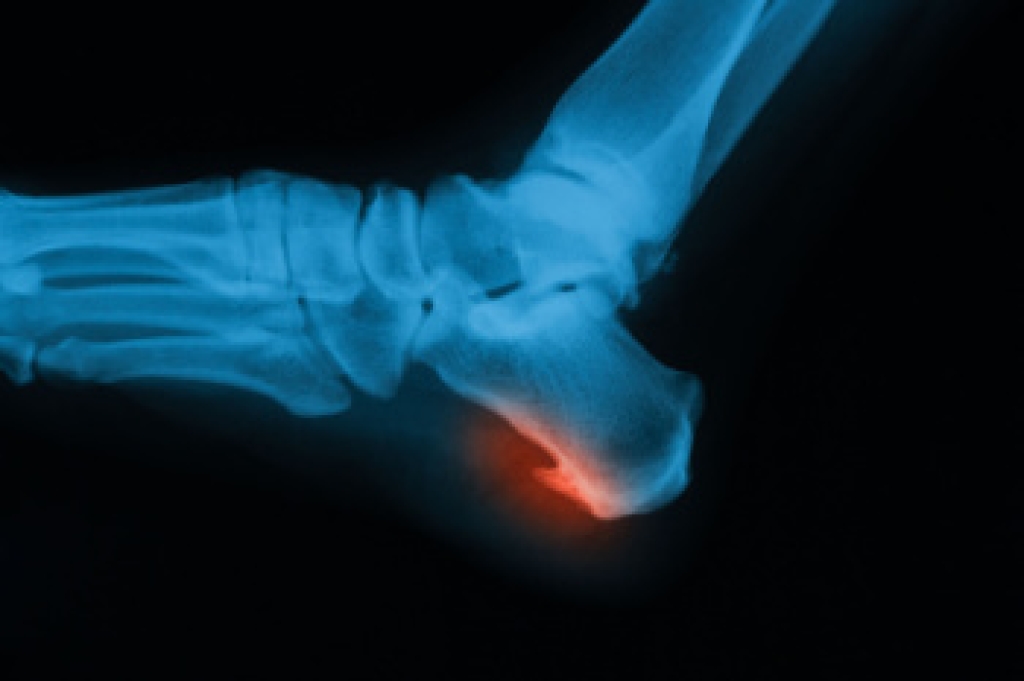

Strong ankles are vital for runners to maintain stability, prevent injuries, and enhance performance. Incorporating specific exercises into your routine can help strengthen the muscles, ligaments, and tendons surrounding the ankles. Simple exercises like calf raises, where you lift your heels off the ground and lower them back down, target the calf muscles and improve ankle stability. Ankle circles are done by rotating your ankles in both directions, which can help to improve flexibility and range of motion. Additionally, balance exercises, such as single-leg stands or using a balance board, can enhance proprioception and strengthen the ankle-stabilizing muscles. Strengthening exercises, such as toe curls and marble pickups, focus on the muscles of the foot and can contribute to overall ankle strength and stability. By incorporating these exercises into your regular training regimen, you can help reduce the risk of ankle injuries while enjoying the benefits of running for improved health and fitness. If you have an ankle injury, it is suggested that you consult a podiatrist who can treat this condition and offer you future running injury prevention tips.